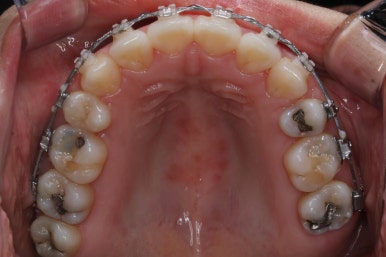

입안 모습입니다.

윗니와 아랫니 모두 각각 보면 가지런해 보이며 발치를 했던 자리도 거의 다 메워져서 양호해 보입니다. 훑어 보면 굳이 더 교정을 해야할 부분이 있을까? 싶겠지만 다음 사진을 보면 알 수 있습니다.